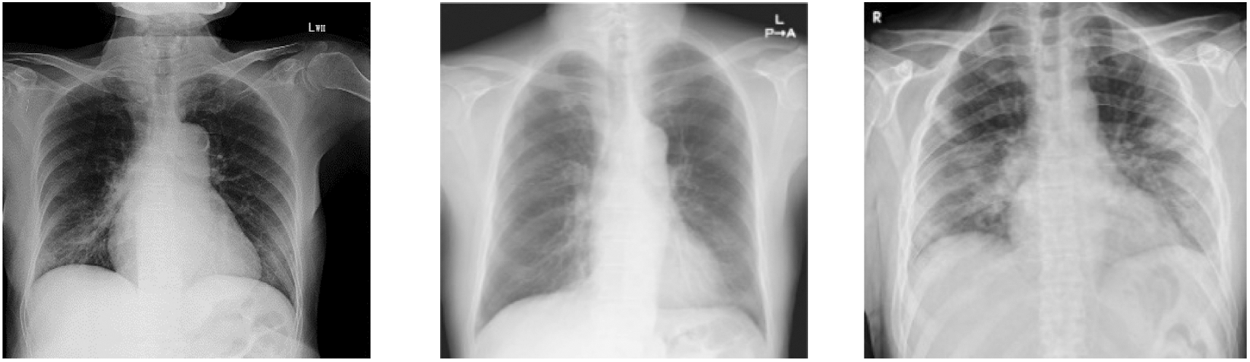

In this group, we have total 130 COVID 19 cases are considered as they belong to 6 or more day’s offsets of symptoms. This Dataset is a subset of dataset which is collected for conducting this research and belongs to COVID 19 Cases of patients which are positive or suspected of COVID-19. Fig. 6 shows Chest X-ray images of Group C.

Figure 5: Chest X ray images of Group C (patients of more 6 days offset of symptoms)